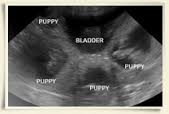

The scan can be started from imaging the urinary bladder first, then examining the uterine body.

The left uterine horn is followed cranially, and then the right uterine horn is followed caudally.

The uterine horns bend in multiple directions rather than lie in a straight line when a large litter is present, and foetuses can be seen literally ‘everywhere’ in the abdomen.

From 35 to around 55 days the foetal skeleton develops and can be seen. This appears white on the ultrasound screen. The head appears circular early on but later the jaws and nasal bones can be identified. The spinal column, pelvis and the ribs can also be seen. The internal organs become more prominent in their appearance. The liver is in the front of the abdomen, being dark grey in appearance, and the fluid filled stomach is often noted just behind this. The heart and some of the great arteries and veins can also be identified. Movements of the pups are often noted and individual limbs can often be seen.

Towards the late stages of pregnancy the bladder which is fluid filled may be seen.